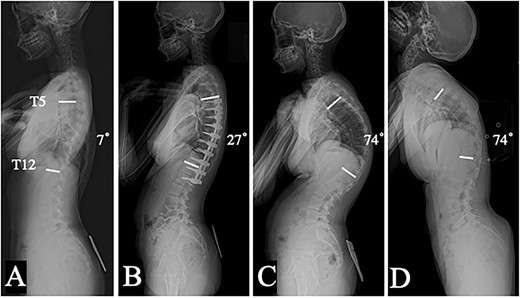

A 13-year-old girl was diagnosed with AIS classified as Lenke type 1A- since her standing radiographs demonstrated the main thoracic (MT) curve of 62° from T6 to L2, the thoracic kyphosis (TK) angle of 7° (Figs 1A and 2A). Posterior corrective surgery was performed at the T5-L2 level to prevent the progression of deformity. The MT curve was corrected to 17°, indicating a correction rate of 72.6%. The TK improved to 27° and acquired physiological kyphosis. At the 1-year follow-up, both the coronal and sagittal alignments were maintained, and the patient restarted sports activities without any impairment (Figs 1B and 2B). However, the patient returned to our hospital complaining of wound swelling 1 month later. Laboratory data showed a mild inflammatory reaction, but magnetic resonance imaging showed subcutaneous fluid accumulation, and its culture revealed Methicillin-susceptible Staphylococcus aureus. Although the infection subsided with debridement surgery and antibiotics, it recurred 3 months later. Inevitably, implant removal surgery was performed after confirming bony fusion by computed tomography (CT) scan. Following this, there was almost no loss of the coronal alignment; however, the sagittal alignment progressively deteriorated (Figs 1B, C). Even though hard bracing was introduced to prevent the progression of kyphotic change, the TK progressed to 74° in a year (Fig. 2C). As a result, the height of the patient decreased by 2.5 cm. The patient complained of back pain in the supine position and the radiograph revealed rigid thoracic hyper-kyphosis that was not corrected by fulcrum bending (Fig. 2D). Therefore, revision surgery was performed 15 months after implant removal. Solid bony fusion was confirmed from T5 to L2. However, slight intraspinal mobility was observed at T7/8 and T10/11, even though the preoperative CT scan showed no clear evidence of pseudarthrosis (Fig. 3A). Pedicle screws were placed from T2 to L3 using an O-arm navigation system due to the significant changes in anatomical structure. Schwab Grade 2 osteotomies were performed again with the removal of fusion masses at multiple levels including at T7/8 and T10/11and the kyphosis was corrected using the cantilever technique (Fig. 3B). At the 14 month follow-up, there was no evidence of recurrence or residual infection, and the MT and TK were corrected and maintained at 5° and 23°, respectively (Figs 4A, B).

Lateral plain radiographs in a standing position: preoperative (A), and 1 year after posterior corrective surgery from T5 to L2 (B); 1 year (C) after implant removal; dorsal flexion in the supine position before revision surgery (D).